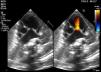

Presentó empeoramiento a las 2h de vida, precisando ventilación invasiva. En la radiografía de tórax (fig. 1) se observaba un corazón en zueco, y áreas de hipersinsuflación pulmonar. Ante la sospecha de cardiopatía congénita se realizó un ecocardiograma (fig. 2), diagnóstico de tetralogía de Fallot (TF) con agenesia de la válvula pulmonar (AVP), con importante dilatación de la arteria pulmonar y sus ramas.